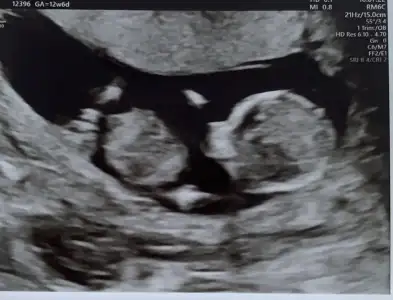

dr soylemeden siz gorun genital nub teorisi ( bebegin cinsiyeti)

Simdi 17 haftaligiz. Bu resimlerdede 12 haftaydi

Attım tekrar bundan baslada yok 12+3

Önce kıza benzettim demiştiniz 😊 bilemiyorum ama bunu dik görünüyor gibi ❤️ dikkatlice bakarsanız görürsünüz ❤️